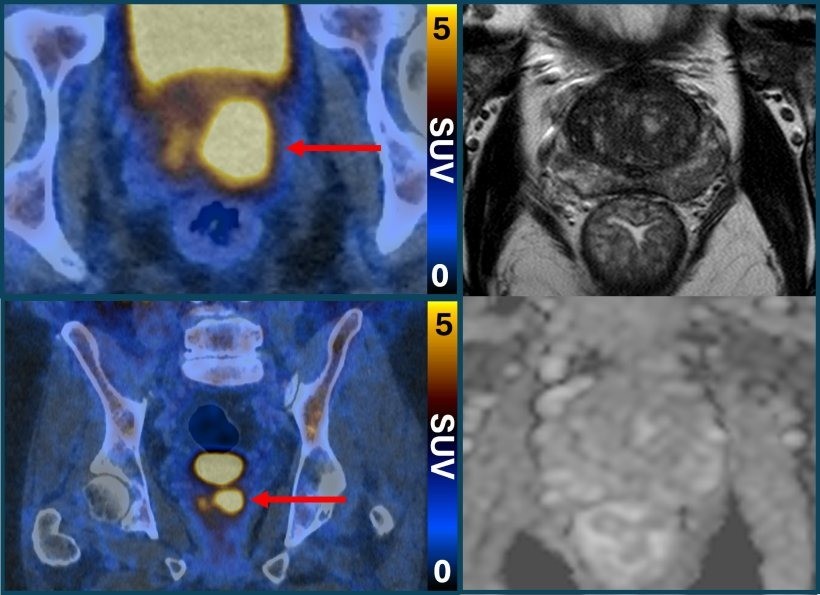

Um novo exame, desenvolvido por pesquisadores europeus, pode diminuir a quantidade de procedimentos inconclusivos e a necessidade de biópsia para detecção do câncer de próstata. Chamado PET/CT com PSMA, ele consegue fazer com que células cancerígenas da próstata mais agressivas apareçam como pontos brilhantes na imagem, o que as torna mais fáceis de identificar.

“A tomografia por emissão de pósitrons (PET/CT) com PSMA faz com que as células do câncer de próstata se iluminem de uma maneira notável, principalmente em casos mais agressivos. É raro ver imagens tão nítidas e com potencial para serem tão úteis na prática clínica. Incorporar esse exame à prática clínica pode ajudar a enfrentar o grande desafio do sobrediagnóstico do câncer de próstata, que leva, na melhor das hipóteses, a tratamentos desnecessários e, na pior, prejudiciais para cânceres que jamais causariam qualquer dano”, afirma o pesquisador James Buteau, médico de medicina nuclear do Peter MacCallum Cancer Centre, na Austrália, que participou do estudo.

O estudo PRIMARY2 descobriu que a tomografia por emissão de pósitrons (PET/CT) com PSMA podia identificar homens que não tinham câncer ou cujo câncer era de tão baixo risco ou crescimento tão lento que provavelmente nunca causaria danos. Ou seja, eles não precisavam de biópsia.